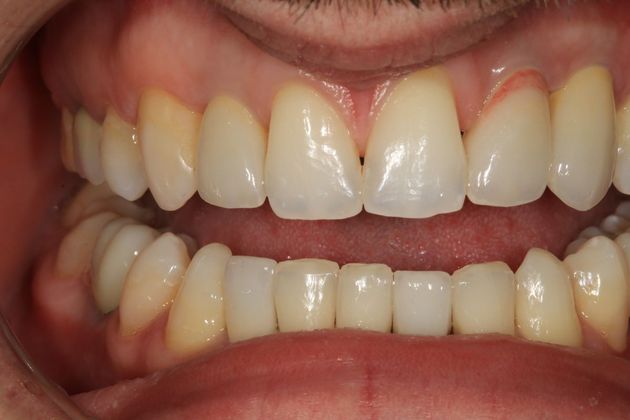

Full mouth rehabilitation. This 20 year old patient had emigrated from Bosnia only a few years earlier with his mother and two sisters after his father had perished in the Bosnian/Serbian conflict. He had severe hereditary dental dysplasia, with multiple retained baby teeth where permanent teeth never formed. He had a total of nine missing teeth, and the teeth that were present were not in their correct positions, leading to a poor bite relationship and multiple large gaps throughout his mouth. He was embarrassed to smile and wanted to know what could be done. His was a very complex case requiring Smile design and; the services of an oral surgeon to take out the baby teeth and strategically place implants at different times of his treatment, an orthodontist to level, straighten and create the proper size spaces for the placement of nine implants, gum sculpting, whitening, and the placement of fillings and crowns on natural teeth, and crowns on the nine implants. It took some time, but he got a great result and the resulting confidence has helped him go to college, get a better job and have a social life! Procedures: Smile design, oral surgery and implant placement, orthodontics, gum lift, whitening, fillings and crowns. TESTIMONIAL:" Dr. Balloch is a very skilled, compassionate and empathetic dentist who develops a personal relationship with his patients. He is (by far) the best dentist that I have experienced in my 85 years. His dental and office staff are equally friendly and professional. Dr.Balloch definitely exceeded my expectations. I highly recommend!"